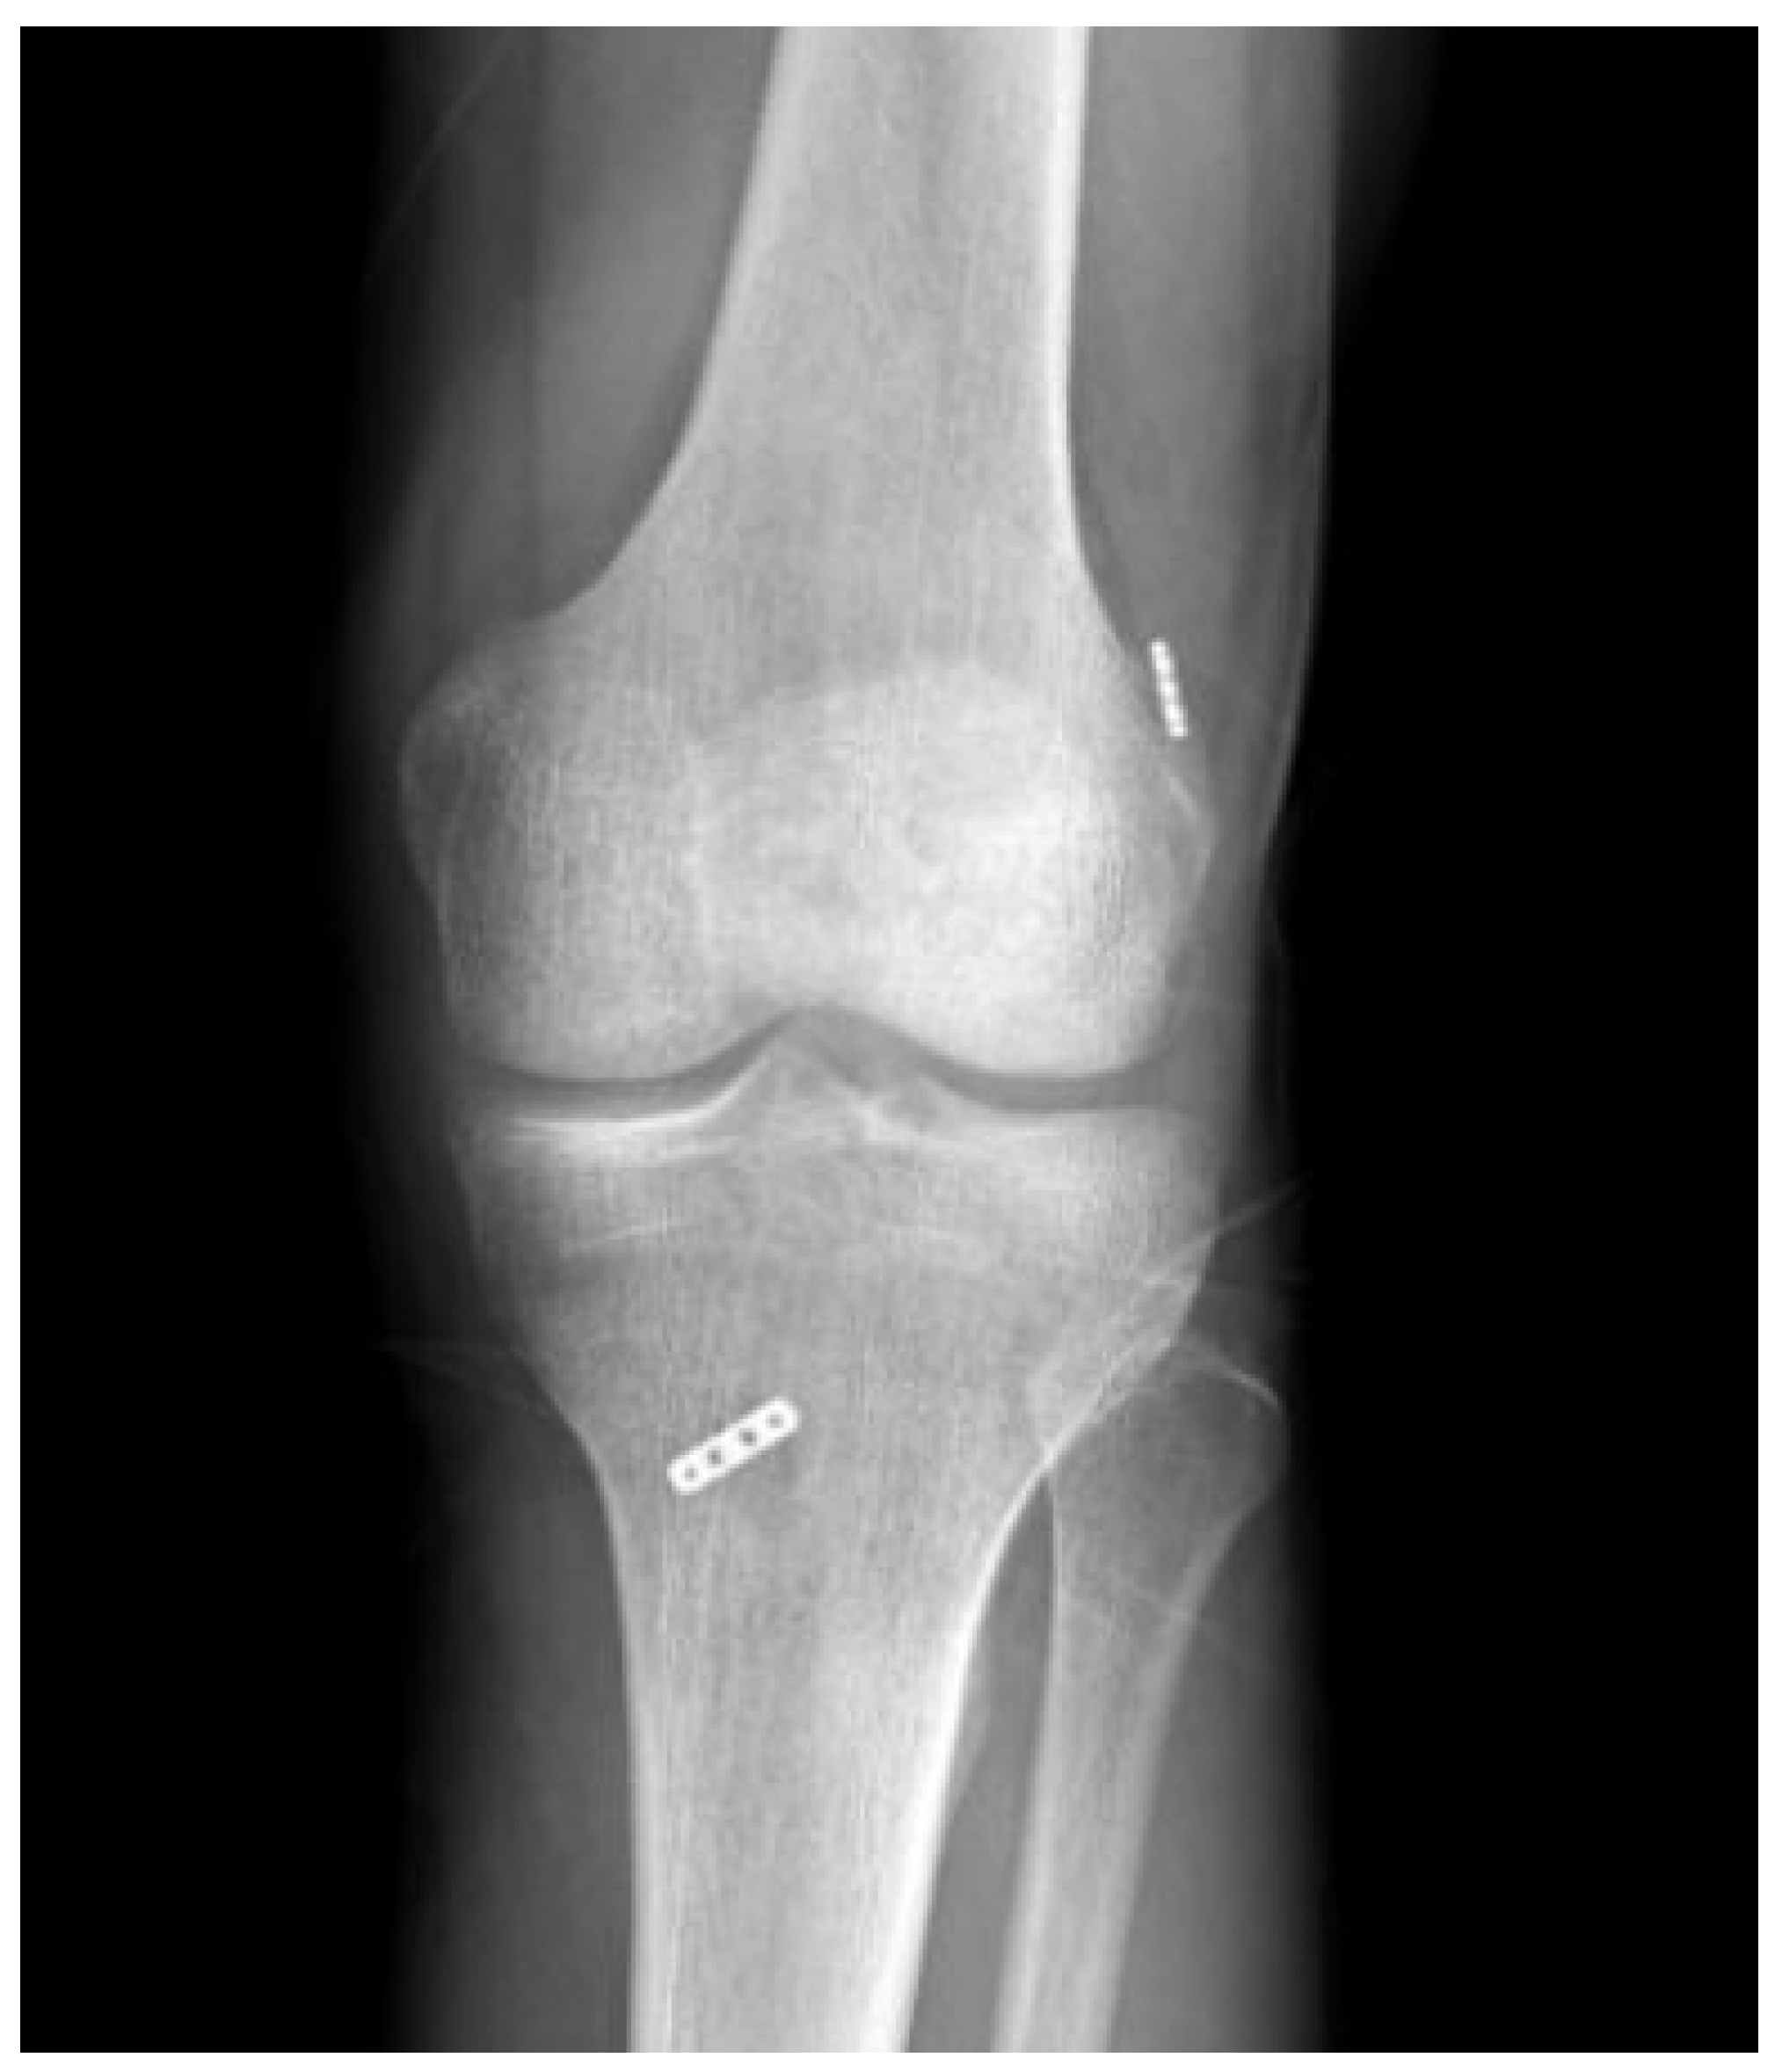

- Mahirogullari, M.; Kehribar, L.; Surucu, S.; Kayaalp, M.E.; Yilmaz, A.K.; Aydin, M. Comparative Results of Anterior Cruciate Ligament Reconstruction with Full Tibial Tunnel: Quadrupled Semitendinosus Suspensory Femoral and Tibial Fixation versus Quadrupled Semitendinosus and Gracilis Suspensory Femoral and Tibial Screw and Staple Fixatio. J. Knee Surg. 2023, 36, 1069–1076. [Google Scholar] [CrossRef] [PubMed]

- Genç, A.S.; Güzel, N.; Yılmaz, A.K.; Ermiş, E.; Pekesen Kurtça, M.; Agar, A.; Ceritoğlu, K.U.; Yasul, Y.; Eseoğlu, İ.; Kehribar, L. Post-Operative Modified All-Inside ACL Reconstruction Technique’s Clinical Outcomes and Isokinetic Strength Assessments. Diagnostics 2023, 13, 2787. [Google Scholar] [CrossRef]